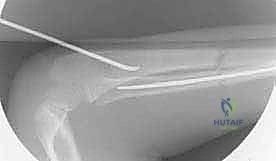

The procedure commences with the establishment of precise entry points, a step that dictates the trajectory of the nails and the ultimate success of the fixation. We typically address the easier fracture first—usually the ulna—to stabilize the forearm segment before tackling the more complex radial reduction. For the ulna, a small 1-2 cm longitudinal incision is made over the lateral aspect of the proximal ulna, approximately 1-2 cm distal to the olecranon apophysis. Blunt dissection is utilized down to the periosteum to avoid injury to the ulnar nerve, which lies medially.

An awl or a drill bit (slightly larger than the selected nail diameter) is used to breach the near cortex. The entry angle is critical; it must begin perpendicular to the bone to prevent skiving, then gradually angle to approximately 45 degrees relative to the shaft axis to facilitate smooth nail passage into the medullary canal.

For the radius, the entry point is established distally. A similar 1-2 cm incision is made over the lateral aspect of the distal radius, proximal to the distal radial physis. Extreme caution must be exercised here to identify and protect the superficial branch of the radial nerve (SRN), which courses directly through this operative field.

The awl is introduced just proximal to the physis, again starting perpendicular and angling proximally.

Prior to insertion, the titanium nails must be meticulously contoured. The radial nail is pre-bent to recreate the normal anatomical radial bow. The apex of the bend should correspond to the location of the fracture to maximize the three-point fixation biomechanics. The ulnar nail is left relatively straight or given a very mild curve to match the native ulnar anatomy.